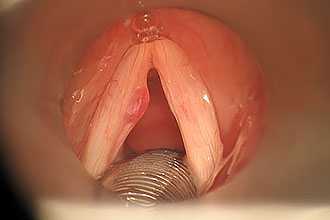

Гортанные контактные язвы представляют собой односторонние или двусторонние эррозии слизистой оболочки над голосовым откростком черпаловидного хряща.

Для диагностики контактных язв гортани выполняется ларингоскопия. Для исключения карциномы или туберкулеза необходимо выполнить биопсию.

Контактная язва гортани

Контактные язвы формируются преимущественно на глубоких внутренних поверхностях глотки и гортани. Поэтому подобные образования становятся диагностическими находками при врачебных осмотрах – без специального инструментария пациент не сможет самостоятельно увидеть такие поражения горла. Тем не менее, причиной обращения к врачу часто становится клиническая симптоматика, с которой связано появление изъязвления:

Контактные язвы голосовых связок — ссадины на слизистой оболочке, покрывающей хрящ, к которому прикреплены голосовые связки.

Врач ставит диагноз контактных язв голосовых связок по результатам осмотра голосовых связок с помощью тонкого гибкого зонда с оптической системой (ларингоскопия).